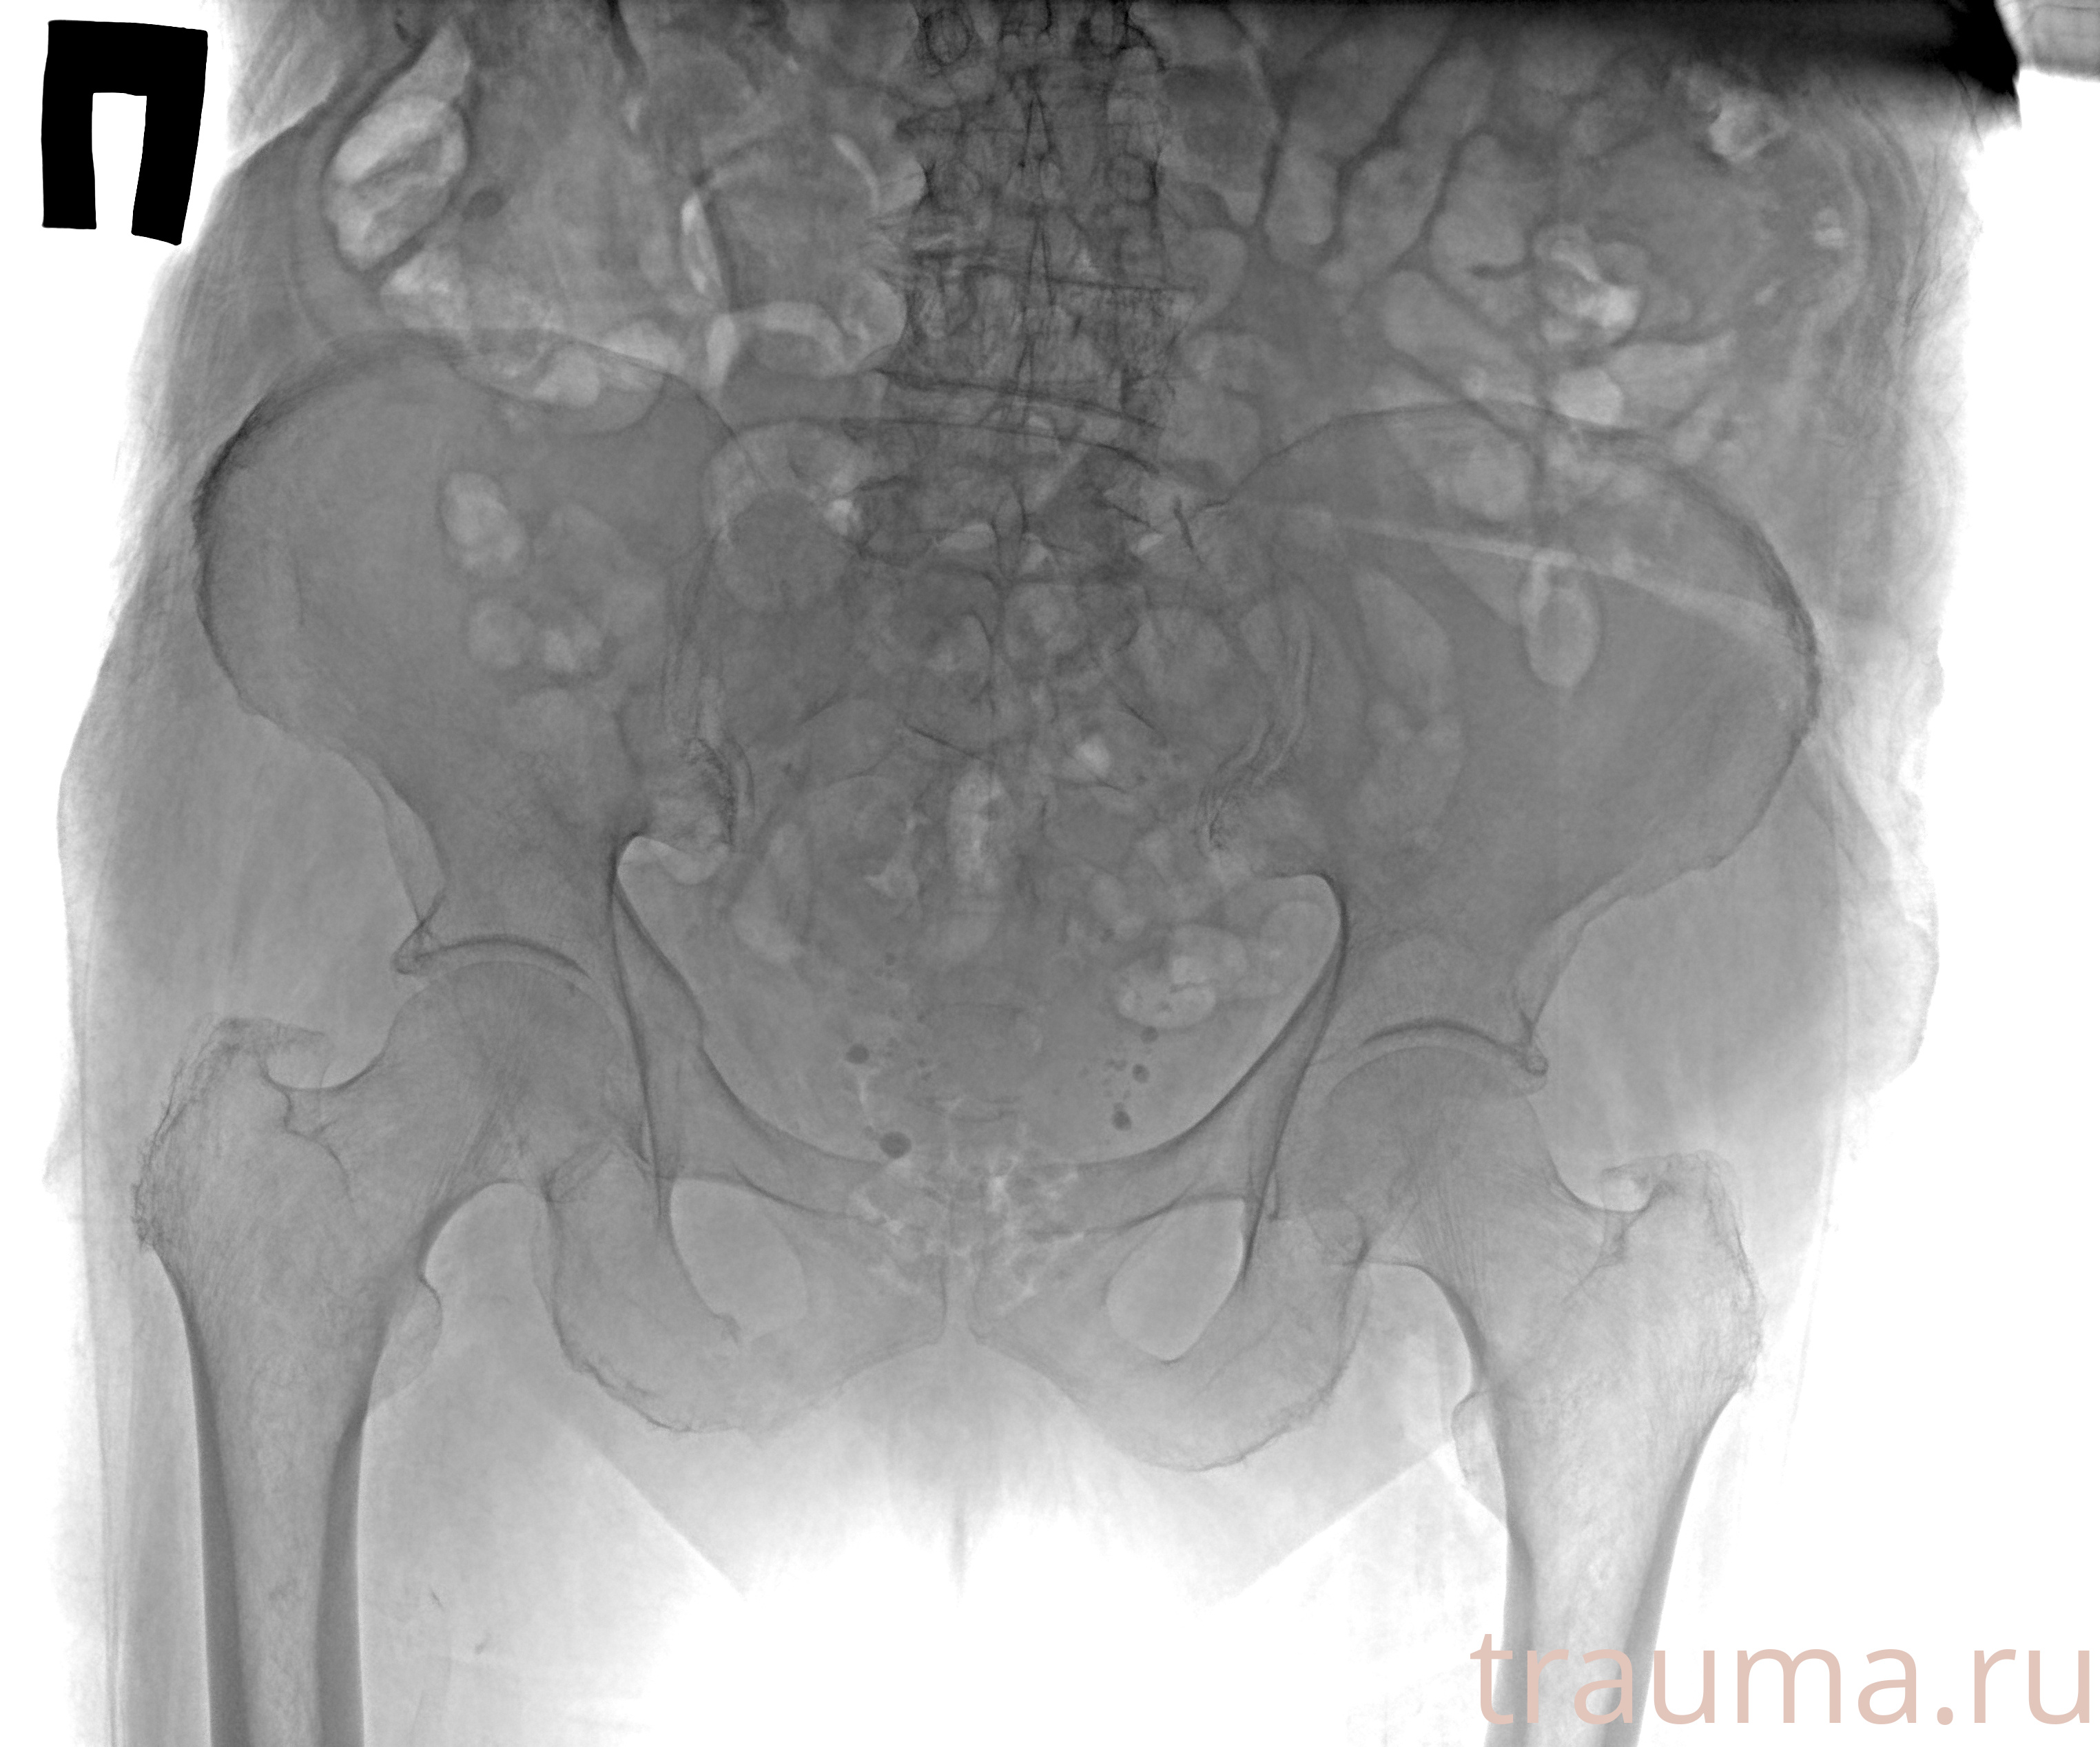

при переломе шейки бедра и пневмонии от компании МосРентген Центр - партнера Института имени Склифосовского